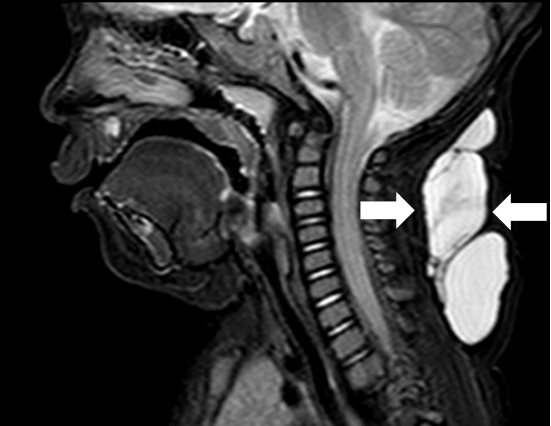

超声难以确诊的病例,或病变周围结构较复杂(如在颈部、纵隔等部位)以及位置较深(如在腹腔、盆腔等部位)治疗难度大、风险高时,往往需加做磁共振检查,更精确评估病情。当影像学检查难以诊断时,也可行诊断性穿刺,若穿刺抽出淡黄色清亮淋巴液即可诊断为淋巴管畸形,若抽出陈旧性血液结合细胞学检查可诊断为淋巴管瘤伴出血。

淋巴管囊肿磁共振检查

通常情况下淋巴管畸形生长缓慢,但是很少自己消退,随着年龄增长病变会越来越大。在遭受外伤、感染及囊内出血或不适当治疗后,常突然增大。如果淋巴管畸形生长在特殊部位,则可能影响容貌,导致身体畸形,压迫重要器官(如气管、心脏等)引起功能障碍,造成长期后遗症,甚至危及患儿生命。故对该病需要采取积极恰当的治疗措施。

纵隔巨大淋巴管畸形压迫气管影响呼吸